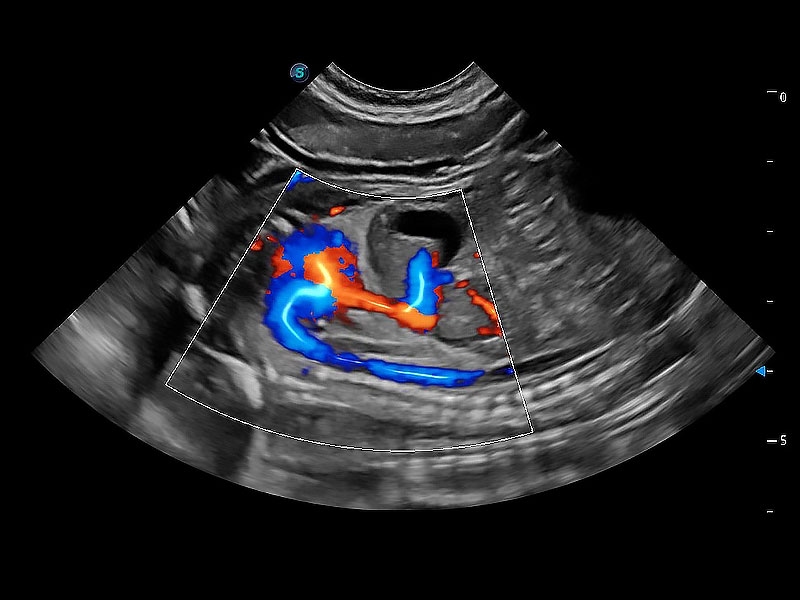

(犬)胎儿主动脉弓立体血流

• Bright Flow 立体血流成像

在传统二维血流成像的基础上,呈现血流的立体感,具有动感的生命力之美。即便是微小的血管也能轻松应对,提高了血流的视觉敏感性。